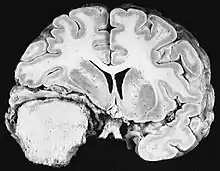

Os tumores de células gliais mais comuns e malignos são os glioblastomas. Consistem em uma massa heterogênea de células de astrocitoma pouco diferenciadas principalmente em adultos. Geralmente ocorrem nos hemisférios cerebrais, mais raramente no tronco cerebral ou na medula espinhal. Exceto em casos muito raros, como todos os tumores cerebrais, eles não se estendem além das estruturas do sistema nervoso central.

O glioblastoma pode surgir de uma forma difusa (II. grau) ou um astrocitoma anaplásico (III. grau) se desenvolvem. Neste último caso, é chamado de secundário. No entanto, quando ocorre sem antecedentes ou evidência de malignidade prévia, é referido como primário. Os glioblastomas são tratados com cirurgia, radioterapia e quimioterapia. Eles são difíceis de curar e há poucos casos que sobrevivem além de três anos.